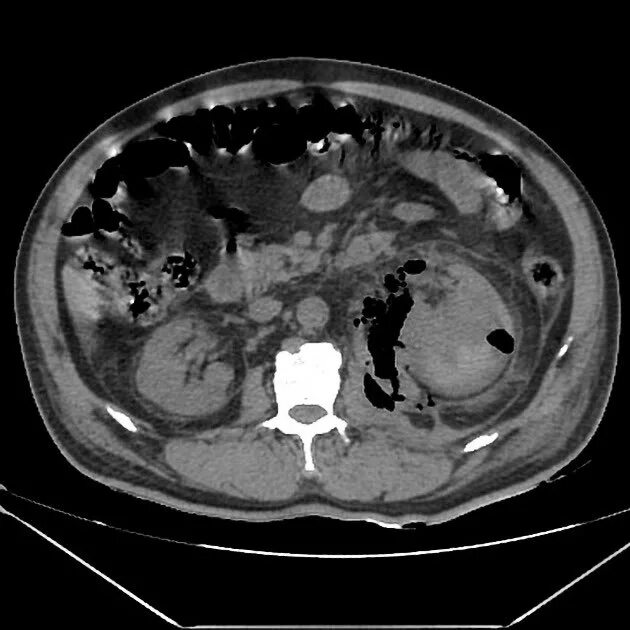

Пиелонефрит кт